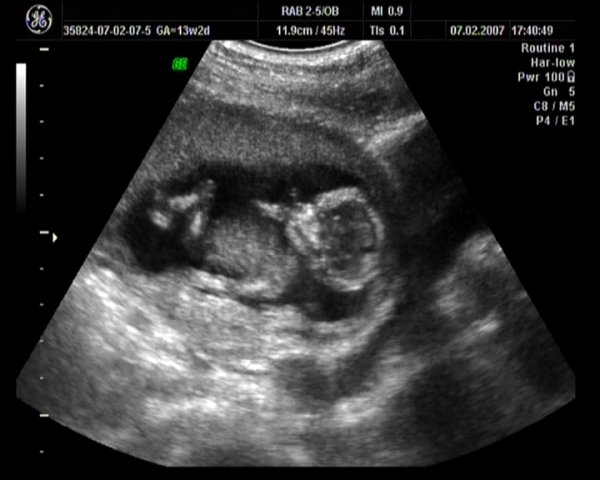

Kriszti nem tudom mi van a pociba.

Remélem hamarosan kiderül. Tegnap apa megkérdezte a babát. 1 rúgás fiú, 2 rúgás lány.

Egyet rúgott, majd hosszú szünet után még egyet.